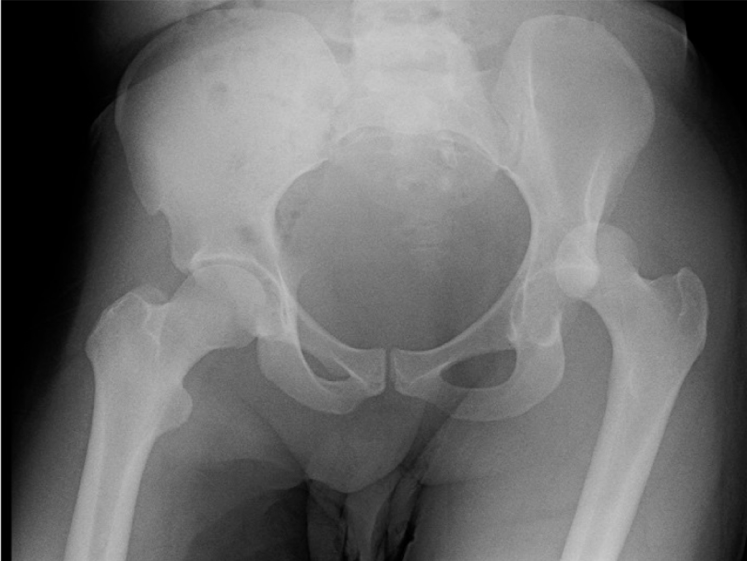

What’s the Diagnosis? Gepost op 9 november 20179 november 2017 door netwerkvsseh What’s the Diagnosis? @emdaily.cooperhealth.org Dit delen: Delen op X (Opent in een nieuw venster) X Share op Facebook (Opent in een nieuw venster) Facebook Delen op LinkedIn (Opent in een nieuw venster) LinkedIn E-mail een link naar een vriend (Opent in een nieuw venster) E-mail Afdrukken (Opent in een nieuw venster) Print Vind-ik-leuk Aan het laden... Gerelateerd